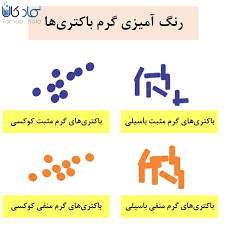

قیمت: 54٬000 تومان - دسته بندی فایل: تحقیقپاورپوینت تشخیص باکتری های گرم منفی (ppt) 23 اسلاید

فروش ویژه پاورپوینت حرفه ای تشخیص باکتری های گرم منفی / تعداد اسلاید: 23 اسلاید